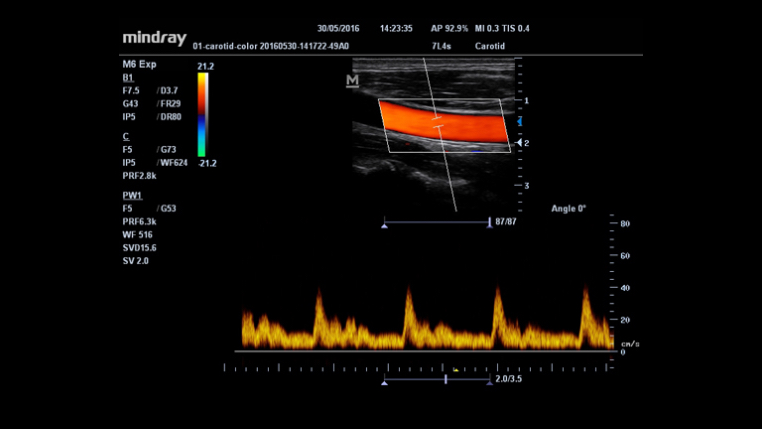

- HR Flow™: Tecnologia avançada para visualização detalhada de vasos sanguíneos pequenos.

- IMT (Medição da Espessura Íntima-Média): Mede automaticamente a parede das artérias, auxiliando em exames cardiovasculares.

- Lineares: L14-6Ns, L14-6s, 7L4s.